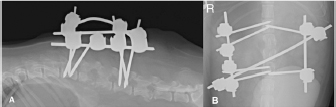

The subluxacion was reduced manually and stabilized using a bilateral and biplanar ESSF. A total of six 2.5mm positive-partially-threaded pins, eight Meynard clamps and three connecting rods were implanted. The positive-partially-threaded pins were inserted in the vertebral bodies of L1 and L4, avoiding contact with the affected vertebrae. Immediate post-operative radiographs were obtained confirming reduced subluxation and realigned vertebrae (Fig. 3).

Fig. 3. Lateral (A) and dorso-ventral (B) postoperative radiograph of the lumbar spine showing the bilateral and biplanar external spinal skeletal fixator after curettage and manual reduction of the L2–L3 subluxation.